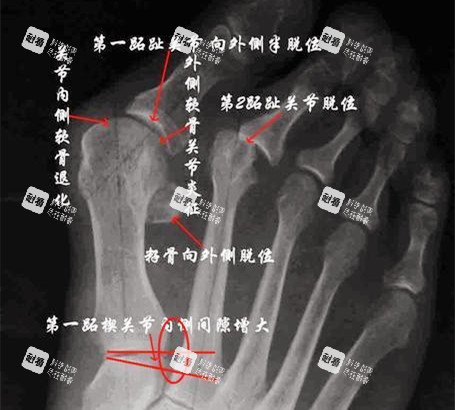

2025年8月,我揣着攒了半年的私房钱,战战兢兢地去了北京圣嘉新。苏医生拿着我的X光片,指着电脑上3D模拟的脚部模型说:“你这属于中度拇外翻,大脚趾偏斜25度,二三脚趾也被挤得变形了,得做双侧矫正,费用大概2.4万。”